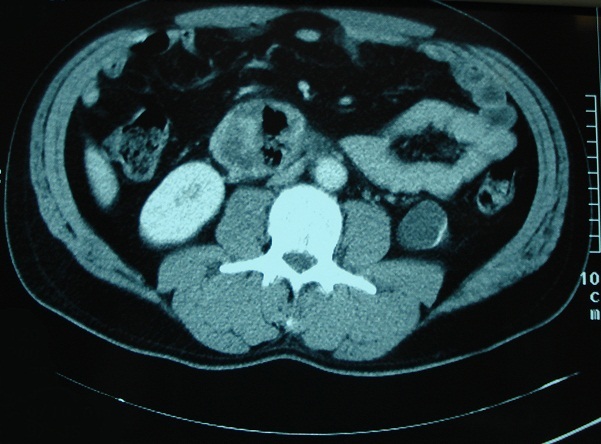

Figure 1.

Coupe scannographique montrant le diverticule à contenu hétérogène avec de l'aire à l'intérieur